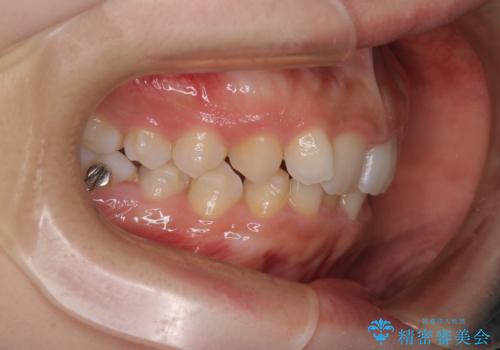

インビザラインで整える深い噛み合わせ

- 患者様は、ディープバイト(深い噛み合わせ)と、咬合平面の左下がりが気になるとのことでご来院されました。診断の結果、非抜歯で治療可能と判断し、透明なマウスピース型矯正装置「インビザライン」を用いる方針としました。治療では、歯列全体の調整を行いながら、咬合平面の水平化を重点的に進める計画を立案しました。2年間で計画的にマウスピースを交換し、左右のバランスと噛み合わせの改善を目指しました。

ディープバイトの矯正は、噛み合わせが深くなりがちなため、細心の注意を払いながら進める必要があります。本症例では、奥歯の高さを調整しつつ前歯の噛み合わせを浅くすることで、全体の咬合バランスを整えました。また、咬合平面の左下がりを修正する過程で、歯列に不均等な力がかからないよう、インビザラインのアタッチメント配置を最適化しました。患者様には装着時間を守っていただき、治療が計画通り進むよう協力をお願いしました。治療終了後には、リテーナーを装着して安定性を確保しました。